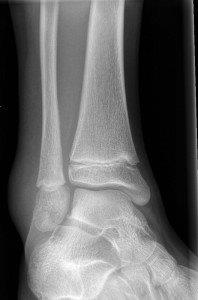

Avulsion fracture of distal fibula

- No formal follow up required.

Salter Harris I fracture of fibula

Undisplaced Salter Harris II fracture of fibula

- Follow up GP 7-10 days for repeat X-ray.

- If displaced, not suitable for CAM Boot.

Undisplaced epiphyseal fracture of distal fibula